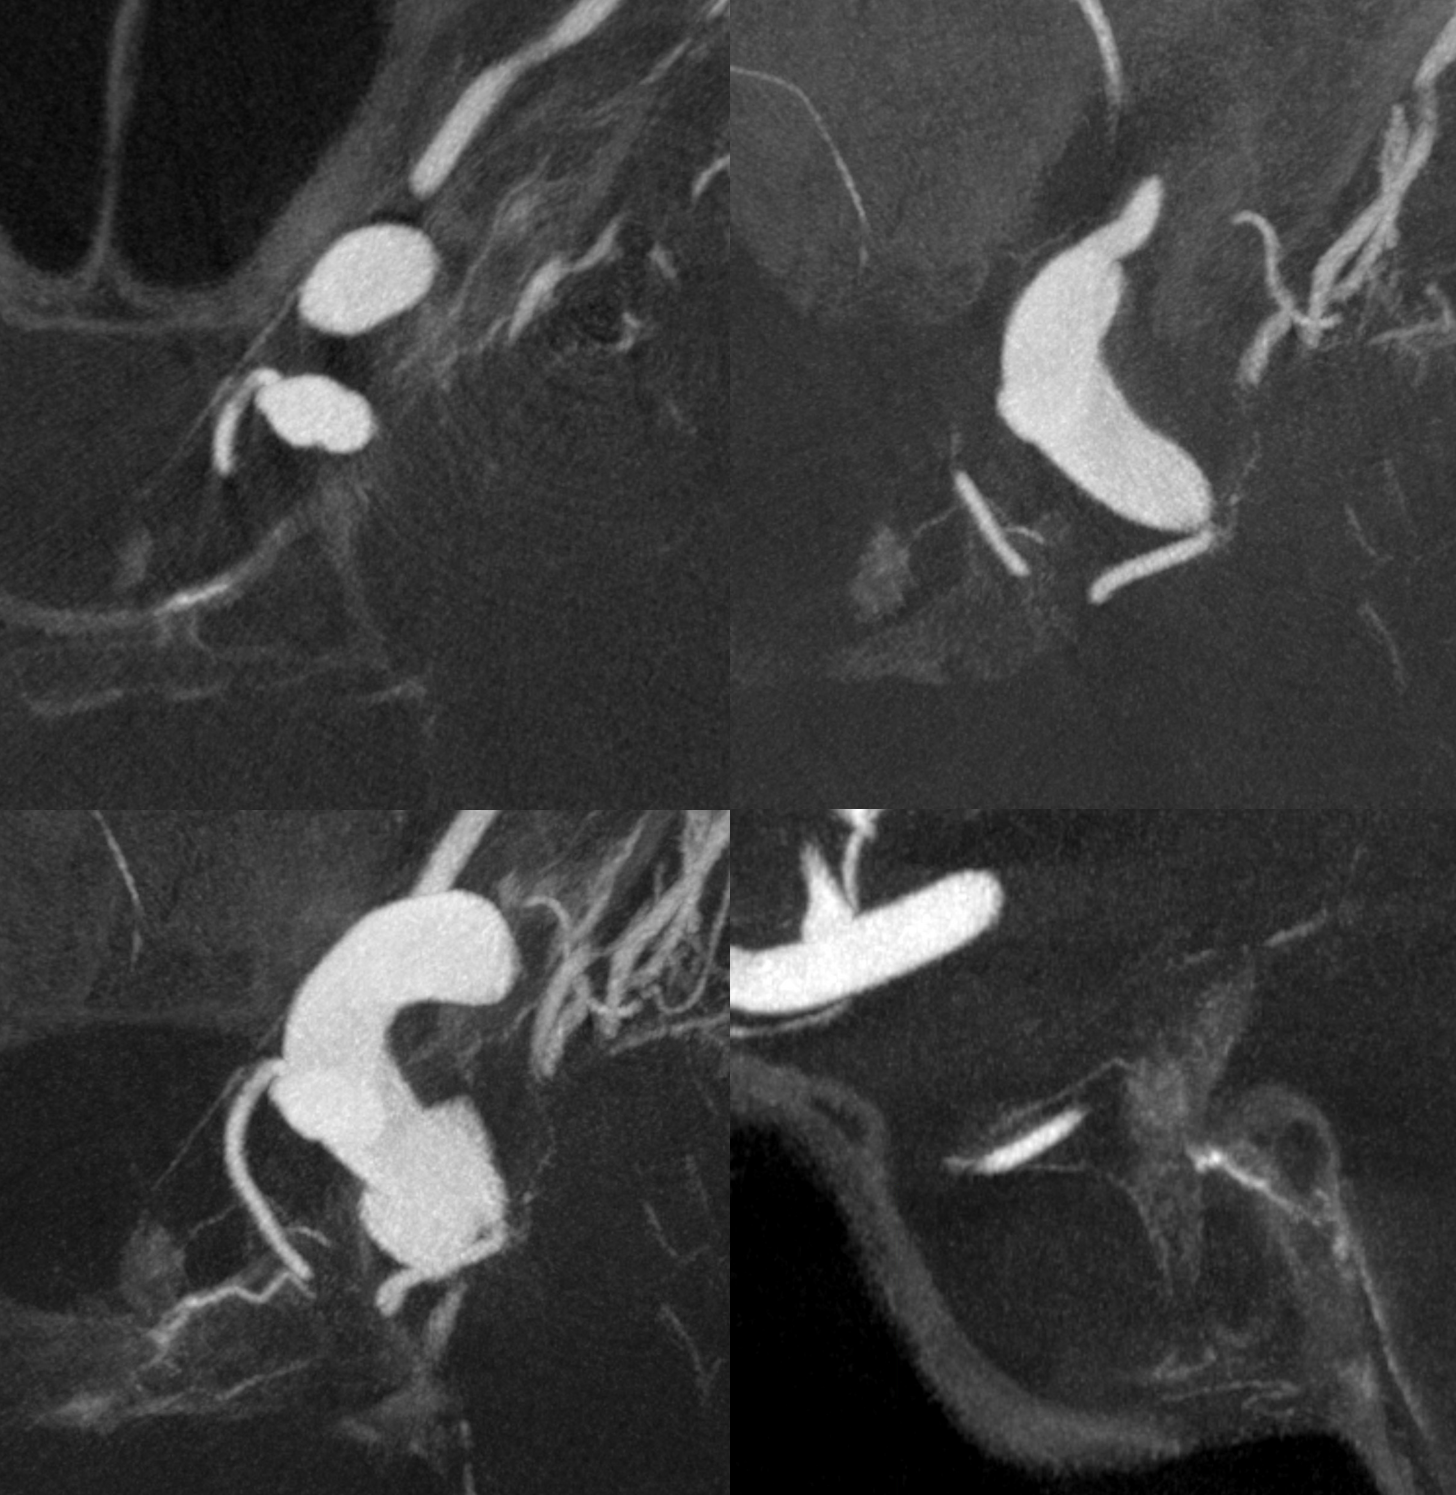

What supplies the bulk of optic nerve? Central Retinal artery is for the distal portion of nerve and retina. What about the rest — intracranial, intracanalicular, proximal intraconal segments? The answer is not clear (let me know if you do), but i believe the bulk of it comes from the superior hypophyseals. It is probably in balance with the recurrent branch of the central retinal artery. Below is an example of an especially prominent proximal-most superior hypophyseal (arrows) supplying the pituitary stalks and optic nerve in the canalicular and intracranial locations. Note how well one can see the branch in coronal view (bottom left image). In this case there are two large superior hypophyseals — the more distal one (dashed arrows) supplies predominantly the pituitary stalk. The inferior hypophyseal artery is marked by arrowhead. Lower right image is coronal.

Movie is the best way

Here too superior hypophyseal (arrow) supply of the intracranial optic nerve (oval) and possibly chiasm is shown definitively (lower right image is coronal)

No annotations

Best seen in this movie (pause to scroll)